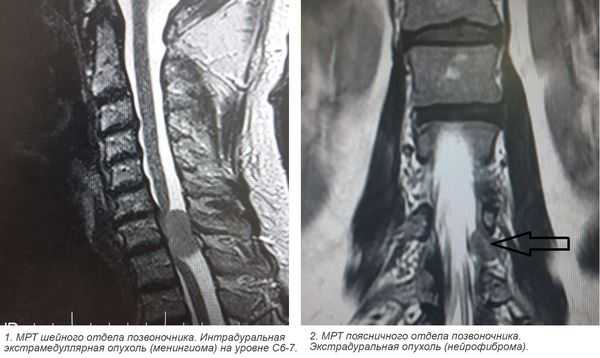

3. Магнитно-резонансная томография (МРТ) с контрастным усилением. На данный момент это основной метод диагностики новообразований спинного мозга. МРТ позволяет визуализировать весь спинной мозг и позвоночник и определить локализацию опухоли. Накопление контрастного вещества определяет не только распространение, но и гистологическую структуру опухоли [5] [6] .